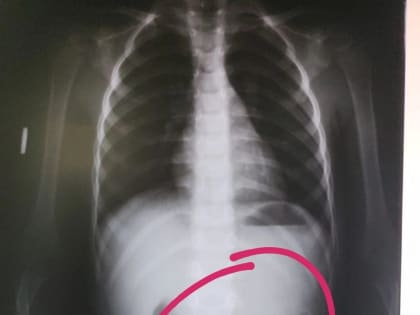

В Башкирии медики обнаружили в животе трехлетнего ребенка цепочку

Фото:Раевская ЦРБ В Башкирии медики обнаружили в животе трехлетнего ребенка цепочку.